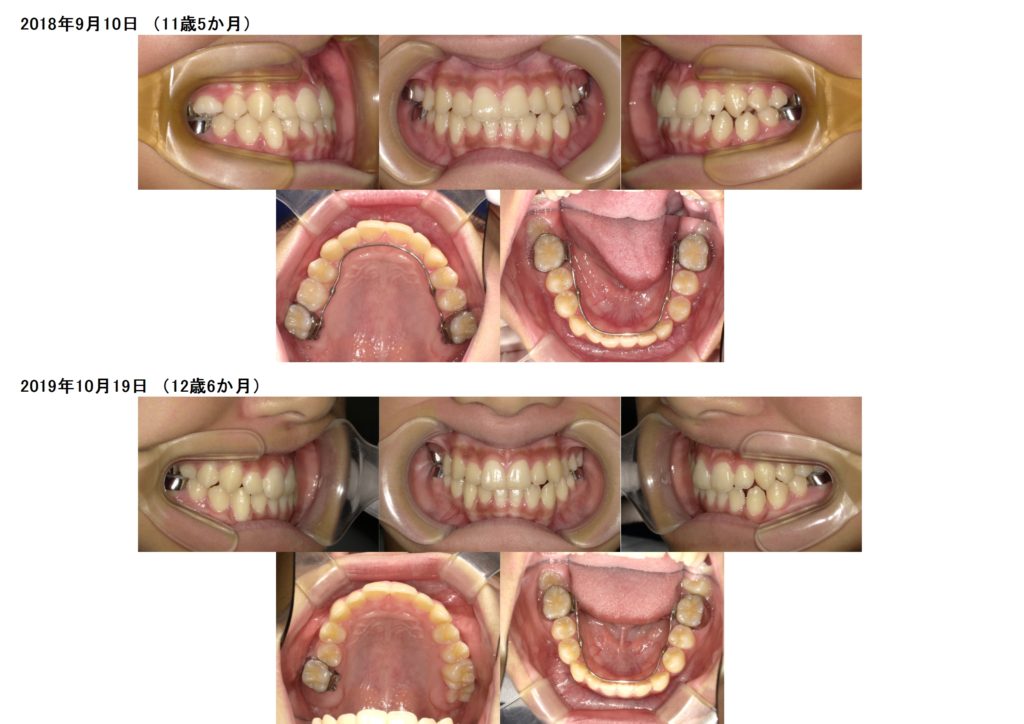

↑初診時の写真と、装置を入れ、永久歯の生えるスペースを確保した写真の比較になります☆

上の写真で分かる所は、上の2番目の歯が中に入っているのと、下の歯も1本完全に中に入っていますね。

↑しっかりと装置を使用すると、永久歯の生えるスペースが上下とも確保できました。スペースが確保できれば、あとは永久歯を待つ期間になります☆